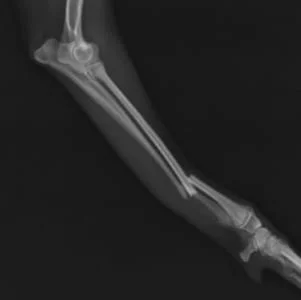

左前肢

左前肢は中和プレートのみなので2期癒合を目指します。

同じく術後19日目 左前肢

左前肢は2期癒合を目指すので、術後2,3週間前後のレントゲンでは

周囲に仮骨形成を認め、また、

骨折部の骨が溶けているように見えます。

これは骨再構築(骨芽細胞、破骨細胞、両方の活動によるもの)

されて起こる現象なので問題ありません。

インプラントの折損、明らかな動揺は認めません。